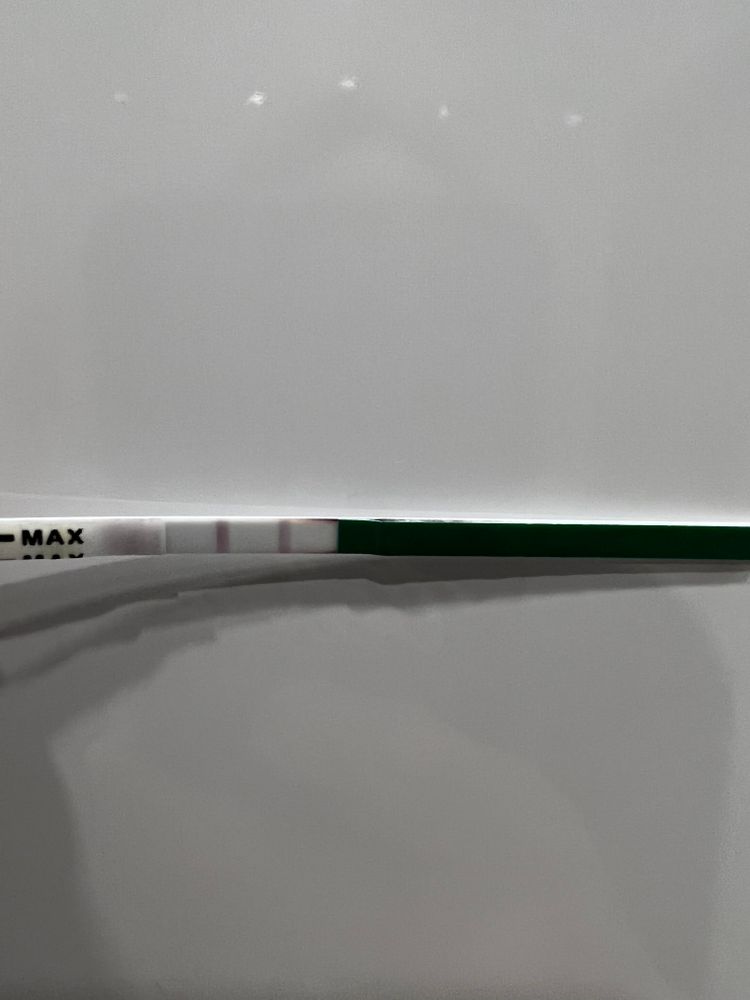

Кстати, фото тестика на овуляцию 15.04 и сегодняшнее узи )))